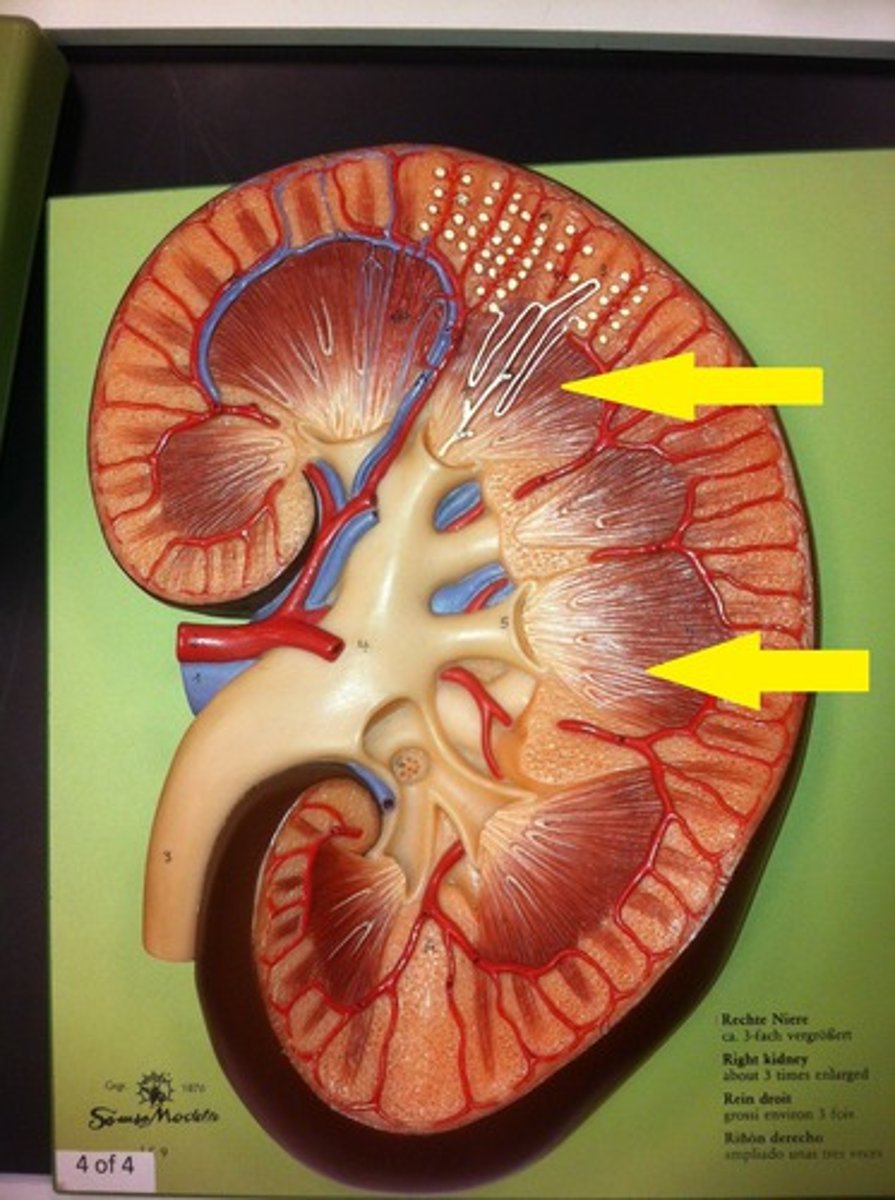

kidney

renal cortex

renal medulla

renal pyramids

renal columns

renal artery

renal vein

segmental

interlobar

interlobular

arcuate